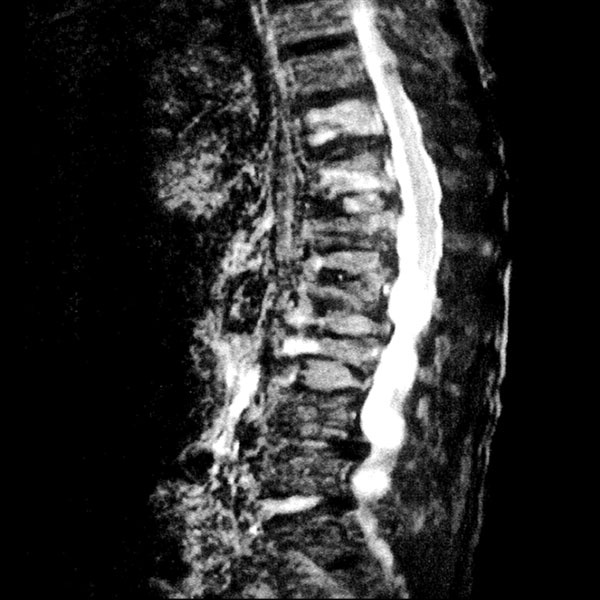

MRI検査

2025年9月16日スタート!!1.5T MRI SIGNA Creator(GE社製)

新しいMRI装置では従来の装置と比較し、高画質、かつ短時間での検査が可能となります。

- AI 機能を搭載:従来の装置と比べかなりの高画質が期待できます

- 従来の装置では難しかった微細な変化の描出にも期待がもてます

- PROPEELR 機能により、動きを抑えたきれいな画像が得られます